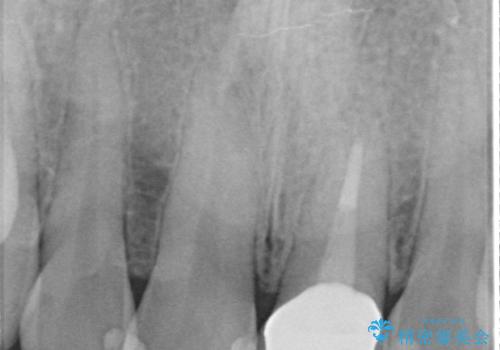

- 前歯の長さが気になるのでセラミックで治療したいといらっしゃった方の症例です。

御希望された再根管治療終了後、オールセラミッククラウンによる補綴を行いました。

今回用いたオールセラミッククラウンはジルコニアフレームという白い素材の上にセラミックを盛っているため、審美性が非常に高いのが特徴です。